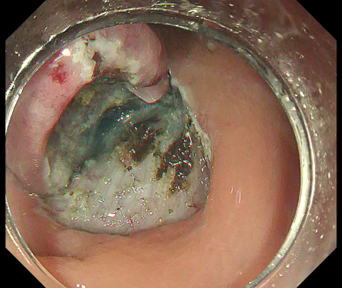

The importance of proper local injection is as described above, but proper “introduction into the submucosal layer”, i.e., entry of the scope tip beneath the mucosal flap, also leads to a favorable result, after which you simply proceed with dissection (Fig. 3). Merely incising the mucosa does not allow introduction into the submucosal layer, even if you try to insert the hood by force. Introduction into the submucosal layer may be possible after removing submucosal tissue a few times in the optimal manner, but this means that you must hold the proximal mucosa so that a large portion of the submucosal layer which you are going to cut is exposed, as shown in Fig. 4. In this figure, the mucosa is carefully held with the DualKnife J’s knob-shaped tip. A similar effect can be obtained by properly using the 6 o’clock position of the distal hood. Even so, it is still not easy to penetrate the layer with a single sweep.

Among the techniques that would facilitate introduction into the submucosal layer, one that can be used with DualKnife J is to “lift up with the tip”, as shown in Fig. 5. Lift the lesion flap with the sheath of DualKnife J and, after visually recognizing the submucosal layer you are going to cut, adjust the position as if aligning the knob-shaped tip with that line. The key here is to achieve maximum deaeration (introduction into the submucosal layer is impossible if the lumen is completely filled with insufflated air) and to gently lift the layer with the tip of the hood (Fig. 6).